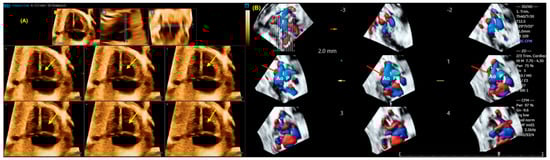

3. Fetal Intelligent Navigation Echocardiography (FINE) and Artificial Intelligence

- Espinoza, J.; Lee, W.; Comstock, C.; Romero, R.; Yeo, L.; Rizzo, G.; Paladini, D.; Viñals, F.; Achiron, R.; Gindes, L.; et al. Collaborative study on 4-dimensional echocardiography for the diagnosis of fetal heart defects: The COFEHD study. J. Ultrasound Med. 2010, 29, 1573–1580. [Google Scholar] [CrossRef]

- Adriaanse, B.M.; Tromp, C.H.; Simpson, J.M.; Van Mieghem, T.; Kist, W.J.; Kuik, D.J.; Oepkes, D.; Van Vugt, J.M.; Haak, M.C. Interobserver agreement in detailed prenatal diagnosis of congenital heart disease by telemedicine using four-dimensional ultrasound with spatiotemporal image correlation. Ultrasound Obstet. Gynecol. 2012, 39, 203–209. [Google Scholar] [CrossRef]

- Karmegaraj, B.; Kumar, S.; Srimurugan, B.; Sudhakar, A.; Simpson, J.M.; Vaidyanathan, B. 3D/4D spatiotemporal image correlation (STIC) fetal echocardiography provides incremental benefit over 2D fetal echocardiography in predicting postnatal surgical approach in double-outlet right ventricle. Ultrasound Obstet. Gynecol. 2021, 57, 423–430. [Google Scholar] [CrossRef]